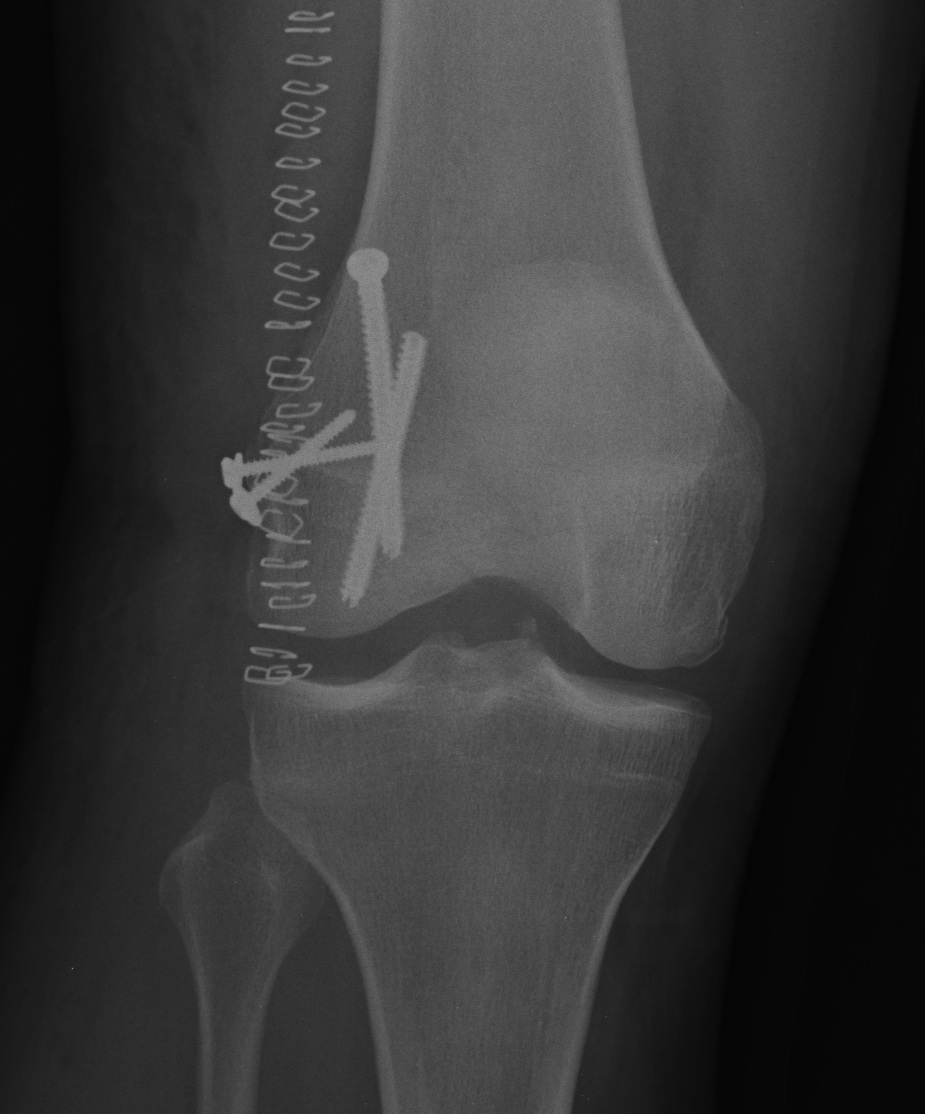

Hoffa Fracture Xray

Coronal plane fracture of distal femoral condyle

Xray

1. Unicondylar

Lateral femoral condyle > medial femoral condyle